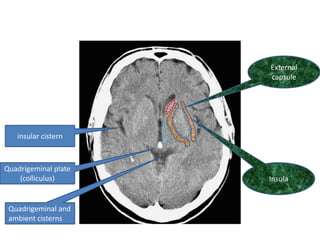

External capsule insular cistern Quadrigeminal plate (colliculus) Insula Quadrigeminal and ambient cisterns